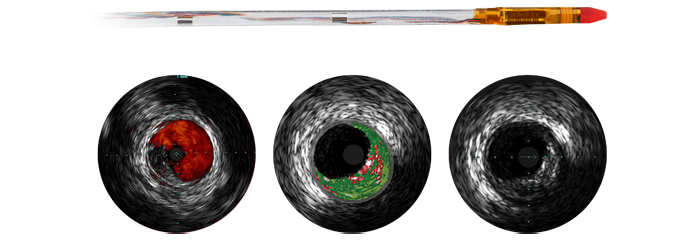

Intravascular Ultrasound - IVUS

See more clearly and improve patient outcomes with informed pre-stent planning and poststent optimization. Map the 3D vessel anatomy to the angiogram* to understand precisely where the disease begins and ends.

Eagle Eye Platinum

Digital IVUS catheter

The Eagle Eye Platinum digital IVUS catheter is the #1 choice of physicians for intravascular imaging (in the US). *As a unique plug-and-play intravascular imaging catheter it is designed for ease of use and deliverability. Features include a soft tapered tip, GlyDx hydrophilic coating for increased lubricity, a long, rapid exchange lumen for improved pushability, three radiopaque markers, and compatibility with IntraSight and SyncVision for co-registration with angiography.